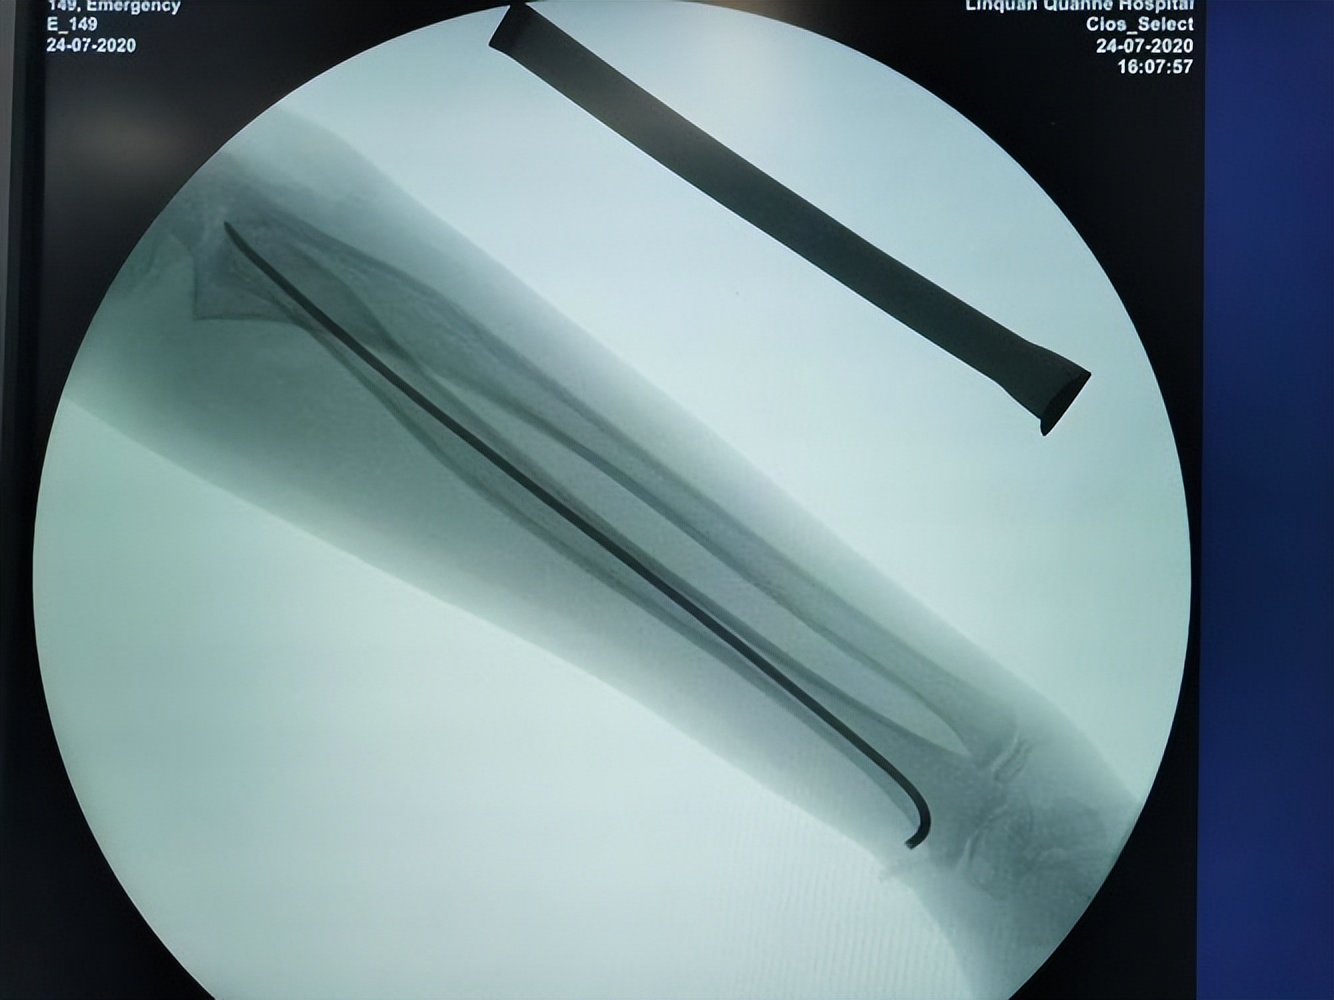

弹性髓内针内固定

近年来伴随着骨科植入器械、手术技术的不断发展,学龄前期儿童股骨干骨折手术治疗也逐渐增多。儿童骨折手术主张微创治疗,注重骨折复位时要求尽量减少手术损伤,弹性髓内针内固定技术为微创治疗的典型代表 :

即利用三点固定原理对骨折弹性固定,防止再移位、成角和旋转,骨折断端无应力遮挡,能促进骨痂生长及塑形,伤肢负重活动早,髋、膝关节功能恢复好 。弹性髓内针固定最佳适应证是股骨干横形、短斜形、螺旋形骨折及干骺端骨折。

近年来弹性髓内针适应证被放宽到长度不稳定型即粉碎性或长斜型、长螺旋型股骨干骨折。 配合尾帽固定能更好的维持股骨干的长度,且能预防弹性钉自股骨远端进钉点退出。如闭合复位仅在开孔处遗留微小疤痕,外观美观 。